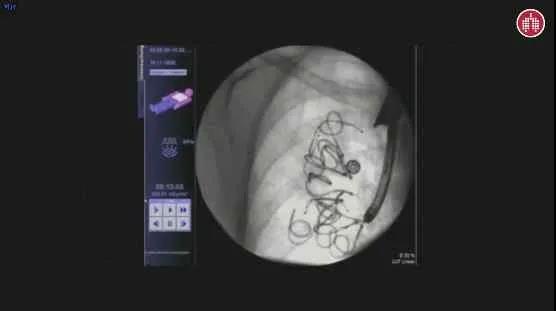

手术在患者全身麻醉状态下进行,在不到1小时的时间内,Eberhardt教授使用支气管镜,于病人右肺上叶部位成功植入10个不同规格的Cinenses™肺减容回力圈。术中无并发症,所有Cinenses™肺减容回力圈均成型良好,手术过程非常顺利。

(图3:单侧肺部植入回力圈的影像)